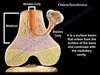

Osteocondroma

Etiopatogenia

Formação de tecido cartilaginoso anômalo na fise

com canal medular e cortical continua com o osso + capa cartilaginosa

Osteocondroma

classificação

Pediculado - base estreita (mais sintomático)

Séssil - base larga (mais malignização)